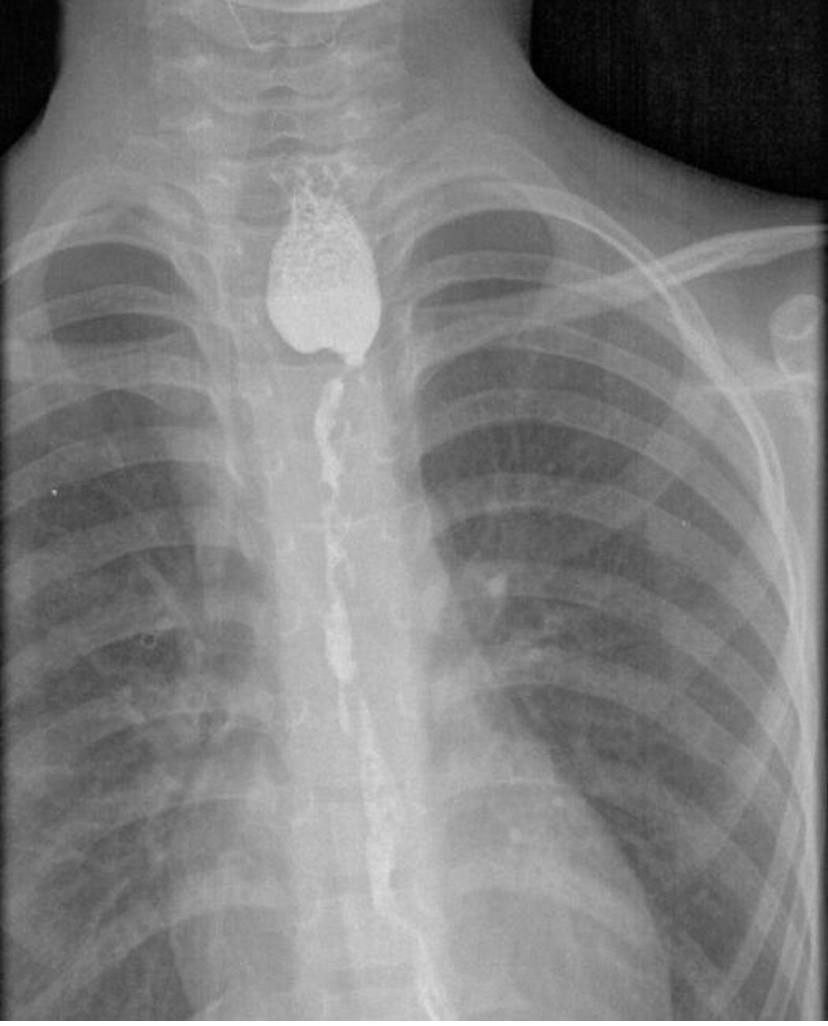

Хирурги Ивано-Матренинской детской клинической больницы сделали 8-летнему мальчику колоэзофагопластику, то есть сформировали искусственный пищевод, рассказали irk.aif.ru в пресс-службе правительства региона. Когда мальчику было 4 года, он выпил средство для очистки раковин и получил сильный ожог пищевода. Его удалось спасти, но несколько лент ребёнок почти не мог есть и месяцами лежал в больнице. Тогда врачи решили провести эту очень сложную операцию.Повреждённый пищевод заменили искусственным, который создали из тканей толстой кишки. Сама операция прошла ещё несколько месяцев назад и с тех пор за состоянием пациента наблюдали. Теперь окончательно ясно: хирургическое вмешательство прошло успешно, ребёнок может нормально есть и живёт полноценной жизнью. Сейчас он учится во втором классе.

Искусственный пищевод Фото: Правительство Иркутской области